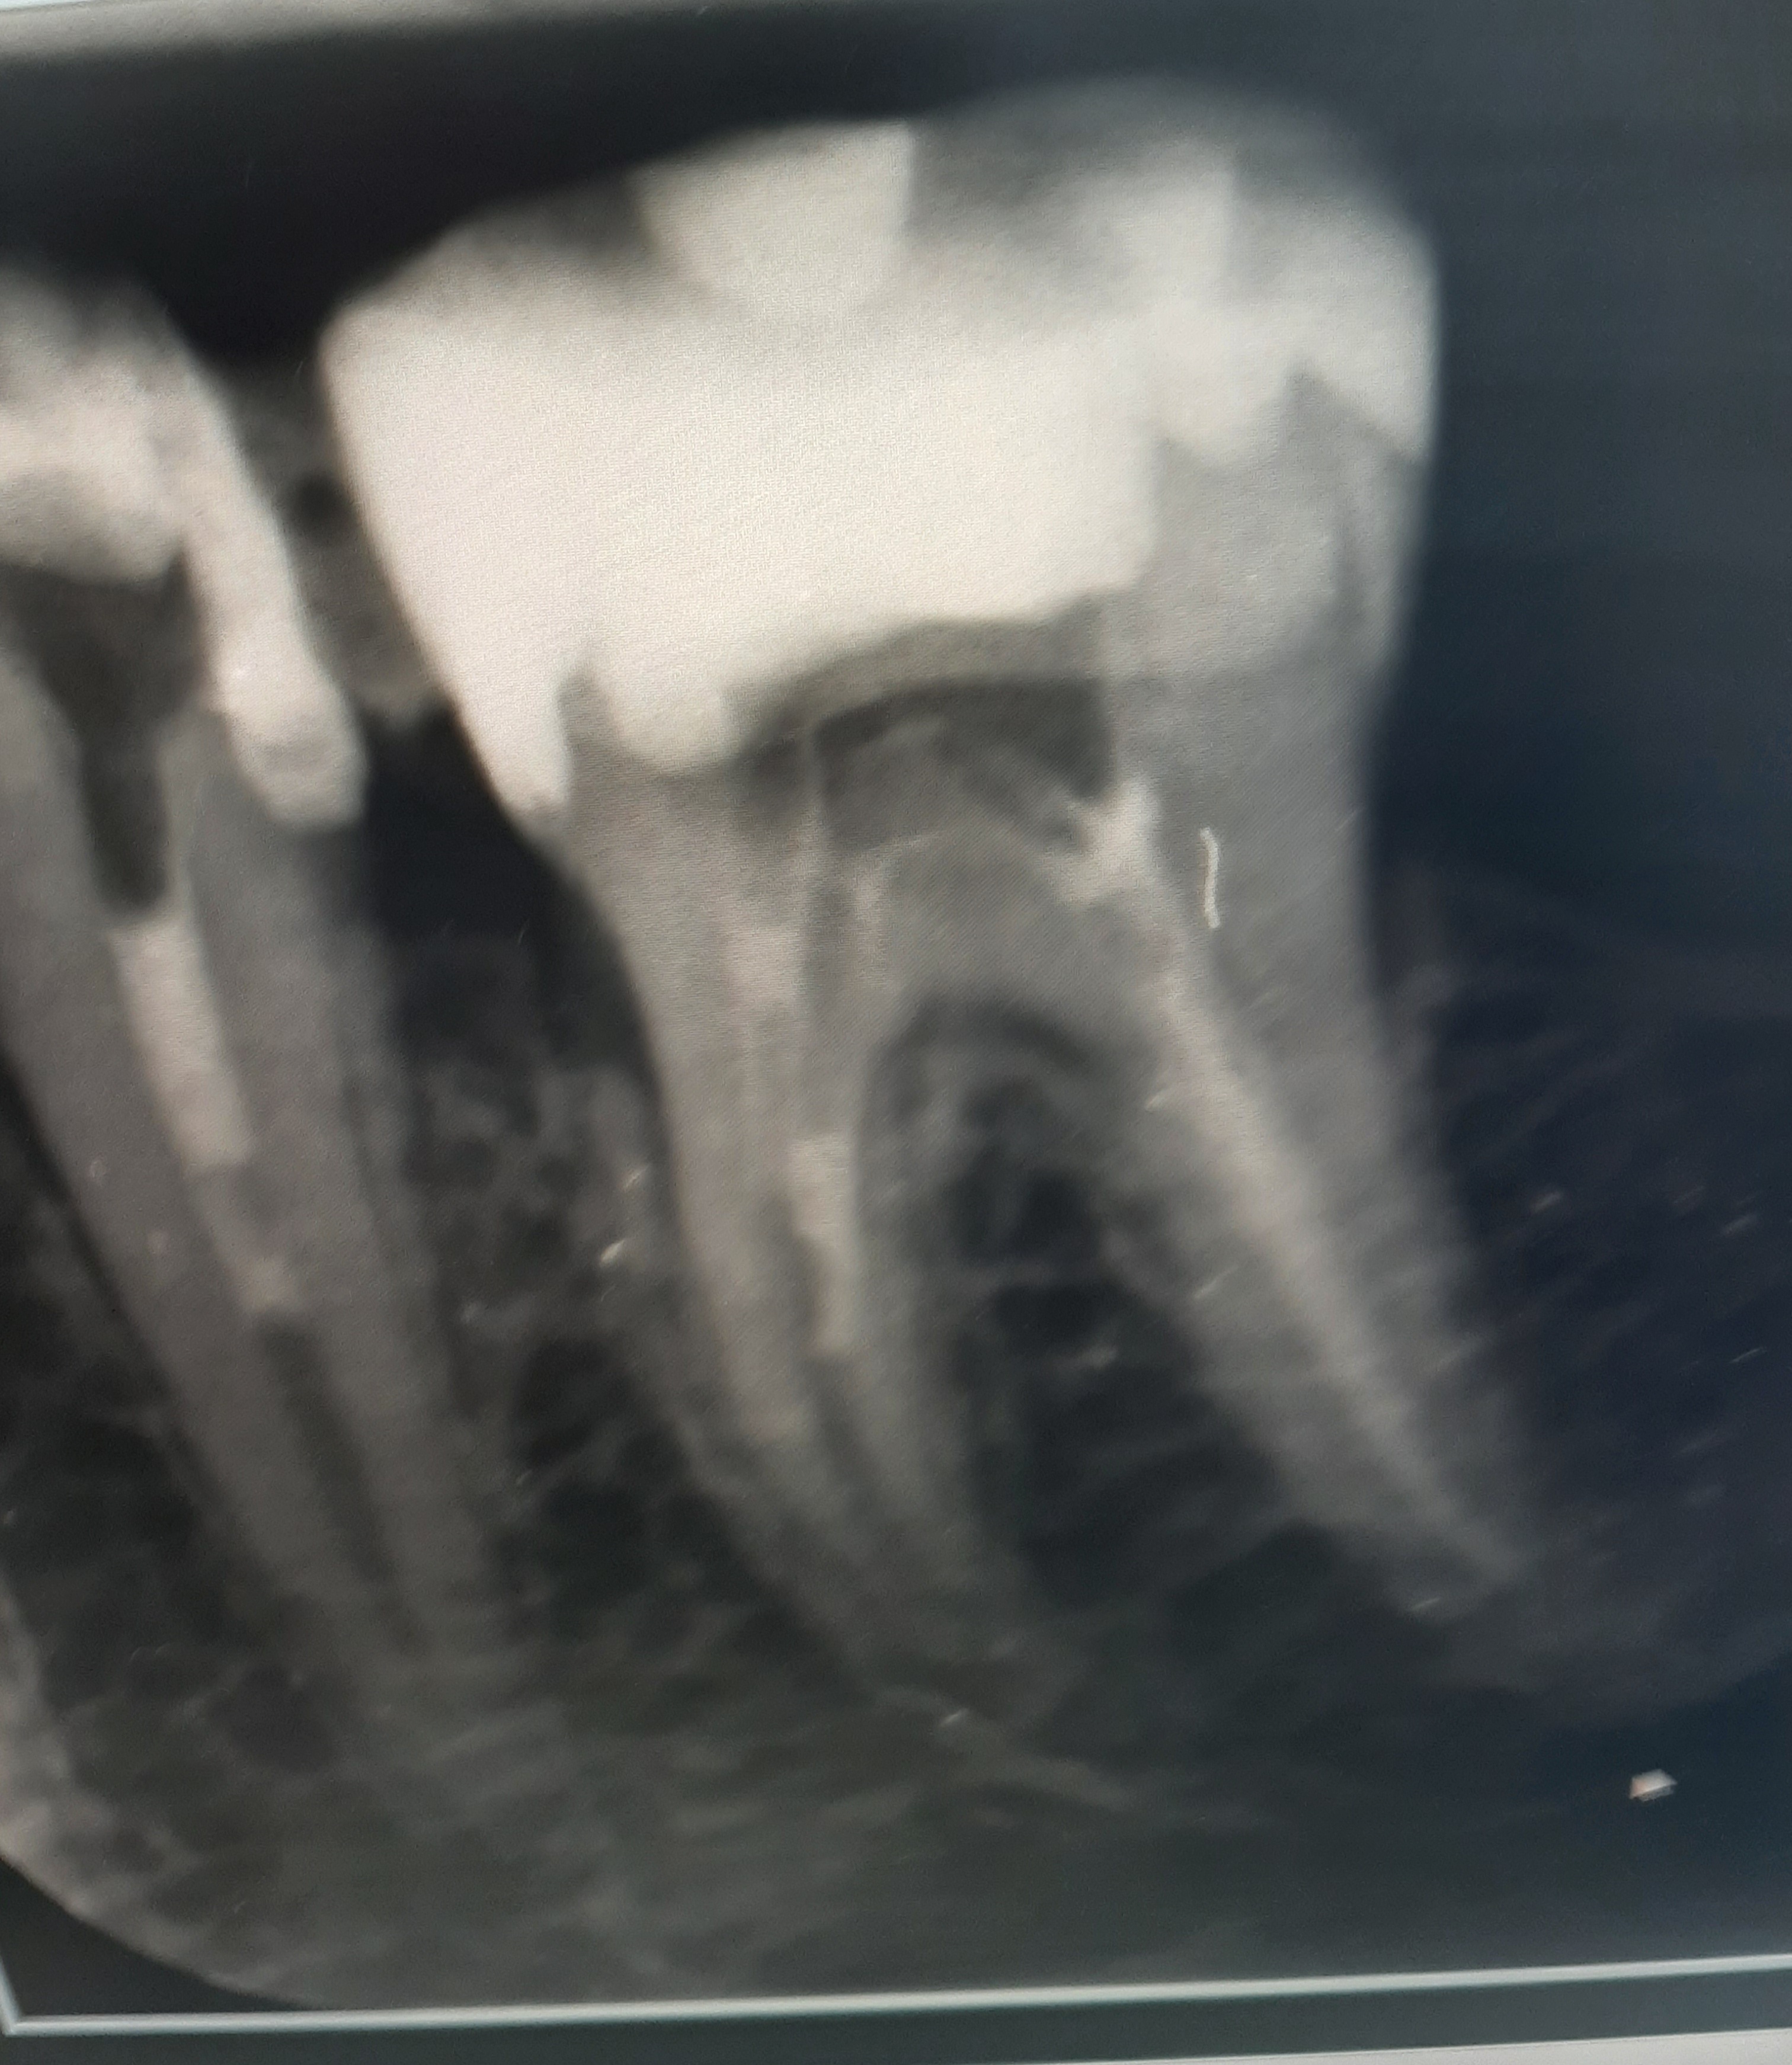

Foto van nu

Nog 1vraag Die lijn dat van…

Die lijn dat van boven naar beneden loopt

Is toch geen tand stuk?

Is dat de botkam?

Heb foto voor en nu ?

Dat is het botkam…

De lijn is botkam. Gewoon…

Foto is te onduidelijk...Zie ik twee breuklijnen of is dit alleen schaduw werking??.